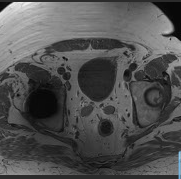

CAZ nr 58: Examinare IRM la pacienții cu proteză de sold

Video 1: achizitie axial T1

Video 2: achizitie coronal T1

Video 3: achizitie axial T2 STIR si axial PD FS

Video 4: achizitie coronal T2 STIR

Discuţie caz nr 58:  La pacienții cu proteză de sold se poate efectua examinare IRM în condiții sigure după 6 luni de la montare cu condiția că pacientul să nu fi fost imobilizat la pat după montarea protezei. Examinarea este indicată pentru evidențierea unor eventuale complicații chistice la nivelul segmentelor osoase, constituirea unor modificări chistice ce evoluează în țesuturile moi de vecinătate  sau pentru altă patologie fără legătură cu proteză. La acest pacient nu se pun în evidență modificări chistice semnificative osoase sau periprotetice de partea dreapta, modificări sugestive pentru necroză aseptică de cap femural de partea stânga cu menținerea sfericității capului femural precum și hernie inghinală stânga la nivelul căreia evoluează cornul vezicii urinare. Se remarcă faptul că achizițiile sunt efectuate cu protocol special pentru minimizarea artefactelor metalice și se recomandă evitarea secvențelor cu saturația grăsimii prin alt procedeu decât cel prin inversie – recuperare (se poate observă diferența în video 3).

DE LUAT ACASĂ!!! Prezența unor proteze de șold sau genunchi nu reprezintă contraindicații absolute de efectuare a examinării IRM; dimpotrivă, examinarea IRM este utilizată la acești pacienți pentru aprecierea complicațiilor precum și pentru evaluarea recuperării musculare după recuperare; în ultimii ani s-au dezvoltat chiar algoritmi AI pentru a aprecia riscul de infecție.